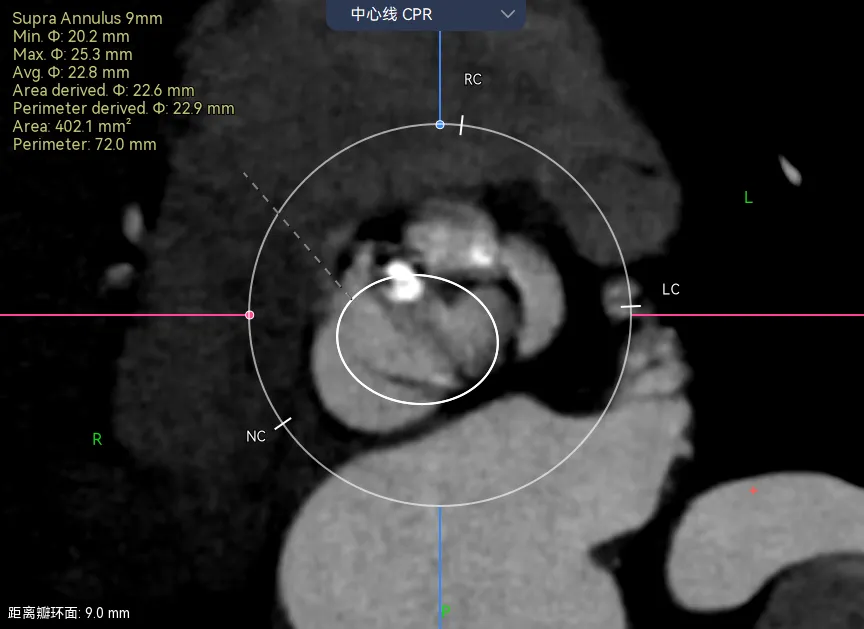

看区域:自展瓣心里一定要有一个锚定区和封堵区的概念 ,一般是在一起的,有时候也不在一起。

比如病例-6.可以看到瓣架比瓣环小了很多,这个时候虚拟瓣环是没有任何封堵作用的。

这个病例是一个明显的type0型二叶瓣挤压瓣膜,锚定区和封堵区都在瓣上,瓣上挤压瓣膜成椭圆导致瓣环位置跟着变椭圆。这时候如果想要没有瓣周漏,就一定要高放让封堵贴合瓣上限制的区域。Oversize是贴不到的。

再一个例子,病例-7,这个更明显了,可以看到虚拟的地方有一半的空隙。

这种病例你想要怎么实现良好的封堵呢?那一定是要在这个地方有覆膜区,而且可以完全贴上,一个层面一个层面看,可以发现找不到一个层面没有空隙的。

这个时候就要预估病人的术后瓣周漏风险了,需不需要一起放个封堵器,箭头指的地方都是导致PVL的地方。